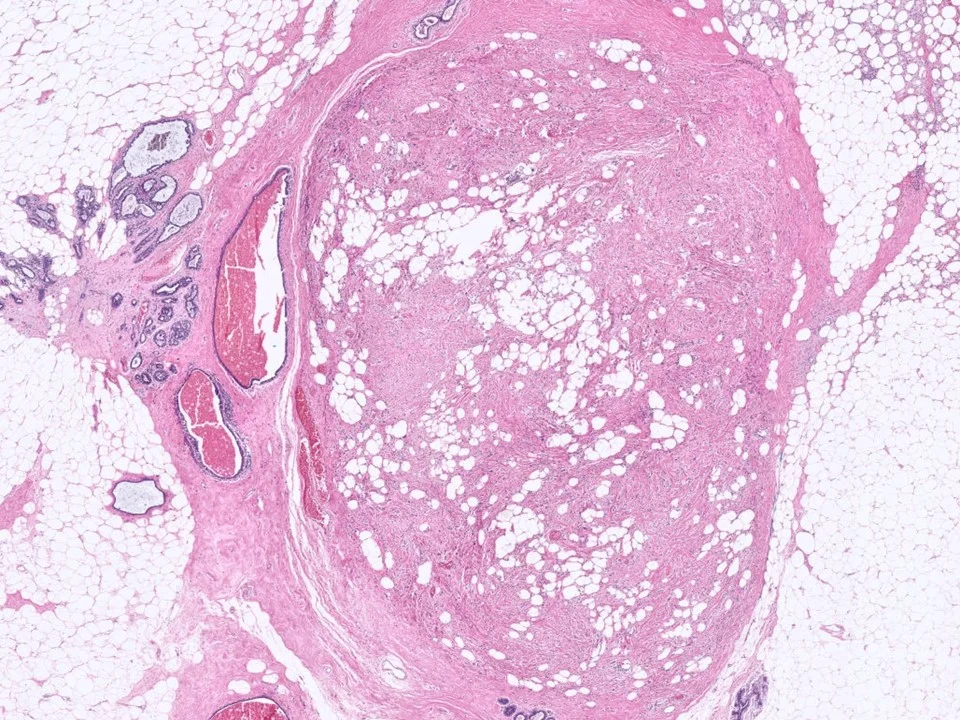

Benign Phyllodes Tumor

Phyllodes tumors are uncommon biphasic lesions that account for <1% of breast tumors. They generally occur in older women as compared to fibroadenomas, and often the patients have a history of a rapidly enlarging tumor. They tend to be larger than fibroadenomas, although this is not a hard and fast rule.

Histologically, phyllodes tumors are characterized by stromal hypercellularity and prominent intracanalicular growth pattern, sometimes with branching, cleft-like spaces.